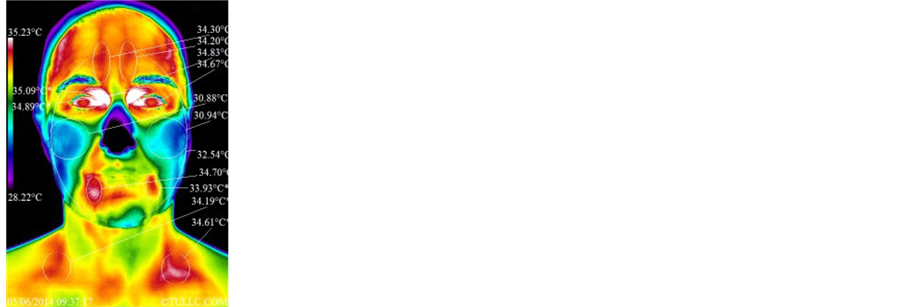

2) Subject B―Female, Caucasian, 49, with history of pain and surgery for right thumb and right lateral breast region

Subject B’s facial thermal images were analyzed using a span of 7.01˚C and positioning between 28.22˚C and 35.23˚C. Figure 7 shows that the temperature of her face decreased significantly (32.54˚C - 31.95˚C = 0.59˚C). Statistical details of the image markers are presented in Table 1. Figure 8 top images show Subject B’s right

All markers of Figure 4 increased in temperature after the grounding session. This is due to the entire torso surge of lymphatic/venous flow routing lymphatic fluids via the inferior vena cava/right subclavian vein/thoracic duct into the left subclavian vein. The upper torso fluids are also routed to the heart via the superior vena cava. This happened while grounded in order to produce a physiological homeostasis/stabilization of core temperature. This subject had what appears to be a purging of lymphatic/venous congestion that not all subjects experienced. As in Figure 4, all markers of Figure 5 increased in temperature. Significant overall head/neck increased temperatures appear to be related to cranial fluids competing with torso fluids that are being overly dumped into the same veins [14] - [17] .

2) Subject B―Female, Caucasian, 49, with history of pain and surgery for right thumb and right lateral breast region

Subject B has a history of right thumb pain with surgery in the region and right lateral breast region pain of a mild intensity. Figure 7 shows significant drop in temperatures over the forehead/eye/oral regions. These indicate significant improved decongestion of the anterior region of the head/neck and significant drop in inflammatory response over the right lower periodontal disorder. There is significant improvement of the lymphatic drainage thermal marker along the right side of the throat to the sternum. Frequently, while viewing the supraclavicular region, one sees a temporary increase in temperature with the surge of lymphatic/venous fluids to the region, but in this case a significantly improved symmetry to the contralateral region and a drop in actual temperature can be seen. This type of drainage and symmetry indicates a healthier pattern overall. Figure 8 shows a significant drop in temperatures over the temporal and oral regions. These indicate improved temporalis myofascial activity with reduced temporomandibular joint compromising effects. There is also a significant reduction in the sternocliedo hypercontractive state. The external jugular vein is hot due to distension of the vein associated with bilateral scalenus myofascitis causing entrapment and back-pressure on this vein. Looking at Figure 9 the diaphragm/hiatal region of the stomach shows minimal changes, radiating lymphatic/venous congestion along the ascending/descending colon into the lower pelvic floor. There is a significant surge in lymphatic/ venous fluids from the lower extremities. The temperature of the colder areas of the abdomen (related to abdominal pressure) increased and this corresponds to a reduction in distention patterns. Overall temperatures improved from the diaphragm to the clavicle, with significant drop in anterior deltoid temperature and improved symmetry of the breasts.

3.3.1. Face Anterior View

Table 1 shows before vs. after temperature marker values from the face anterior view thermal images for within and between group comparisons. Temperature differences above 0.5˚C are considered significant as per the discussion in Section 2.4 Statistical Analysis. From Table 1, it can be seen that each subject had a statistically significant change in average temperature marker after the grounded session or the sham-grounded (see columns with heading “Diff”). Looking at the last 3 columns entitled “Grounded Group Avg.” and “Control Group Avg.”, which present the average temperature of the markers of the 3 subjects in their respective group, the grounded group shows a decrease in average temperature of less than 0.5˚C (0.25˚C) after grounding that is barely statistically significant (p = 0.0423) while the sham-grounded (control) group presents a decrease in temperature above 0.5˚C (0.64˚C) that is highly statistically significant (p = 0.00008). Between group comparisons show that the average temperature of the face for both groups before the session was similar (p = 0.564) and this was also the case after the session (p = 0.958). In other words, the statistical tests could not rule out that the two groups had the same temperature before and after the session. However, the average temperature difference (last column) is significantly smaller for the grounded group (p = 0.002), meaning that the smaller decrease in temperature observed for the grounded group compared to the control group is not a chance happening but that grounding must have played a significant role in producing that difference in average temperature between groups. Left to right differences before and after grounding and between groups were also calculated but did not show any significant result for the face anterior view thermal images.

4.2. Statistical Analyses

In Table 1, it can be seen that the average difference in temperatures of the front view of the face decreased after both the grounded and sham-grounded sessions (p = 0.0423 and p = 0.00008, respectively). However, the decrease in temperature was more than 0.5˚C for the sham grounded group only (0.64˚C vs. 0.25˚C for the grounded group). It is also noted that there was a statistically significant difference between groups (p = 0.002), indicating that the temperature decrease of the sham-grounded group is statistically significantly larger than that of the grounded group. Subject A was the only subject with an increase in temperature of the face and the increase was significant (greater than 0.5˚C) and as such is the main contributor of the reason why the temperature decrease of the grounded group was less than that of the control group. However, subject A was chosen because it represented other subjects with similar increases after a grounding session. This was not seen for the control group i.e. no control subject showed an increase in facial temperature after a sham-grounding session. In this regard, the results of Table 1 are a reflection of the trends seen in our grounded subjects compared to the control subjects as a whole. In summary, Table 1 results indicate that, in average, the front of the face cooled a little for the grounded group while it cooled a lot more for the control group, in fact so much more that it can be said that the cooling seen for the control group is significantly different from that of the grounded group.

Table 2 shows a decrease in the average temperature of the left and right sides of the face combined. The decrease was negligible for the grounded group (0.04˚C; p = 0.878) while it was significant for the control group (0.42˚C; p = 0.00256). There was a statistically significant difference in temperature decreases between groups (p = 0.0017), indicating that the temperature decrease of the sham-grounded group can be considered significant while that of the grounded group is not. The minimal changes in facial temperatures seen in Table 1 and Table 2 for the grounded group are an indication of higher blood flow to the face for that group.